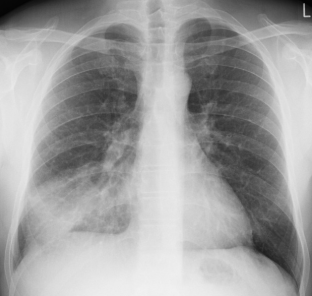

Chest pain, breath shortness, cough and hemoptysis

Disease Specialty: Pulmonology

Image Type:

CT Scan